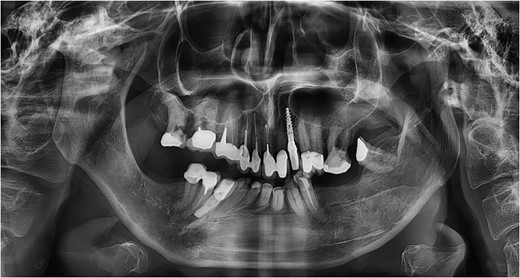

Clinical examination confirmed limitation of mandibular mobility with 16 mm interincisive mouth opening, 2 mm right-sided laterotrusion and inability for left-sided laterotrusion or protrusion. An Angle class II.1 malocclusion was present. The lower dental midline had undergone a right-sided shift, an occlusal cant was present as well as a right-sided crossbite. Extra-oral examination revealed facial asymmetry with skewing of the menton towards the right side and a short posterior facial height. A panoramic radiograph illustrated extensive dysplasia of the right condyle–fossa complex (Fig. 1). Additional CT and MR imaging was performed. These confirmed upward condylar displacement of 11.5 mm into the middle cranial fossa on the right with extensive osseous remodeling and upward relocation of the right inferior temporal gyrus. Three-dimensional rendering using Mimics® medical image processing software and CT–MR image coregistration based on mutual information [2] were performed to add visual information regarding to the severity of the trauma (Fig. 2).

Panoramic radiograph at the age of 63 illustrating a mandibular asymmetry with extensive remodeling of the right condyle–fossa complex. The mandibular condyle and adjacent temporal bone structures can no longer be discerned. Note the superimposition of a silicone soft tissue implant as a noninvasive approach to compensate for the mandibular asymmetry.